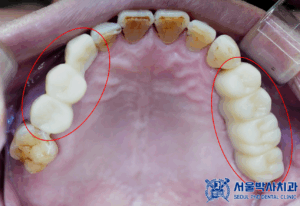

이번 환자분은

오른쪽 치아들이 많이 흔들려서

임플란트 상담을 받기위해

치과의사인 지인 소개로

산성역치과 서울박사에

내원해주셨습니다.

확인해보니,

치아가 상실된 부위도 많고

남아있는 치아들이

흔들리는 상황이였는데요.